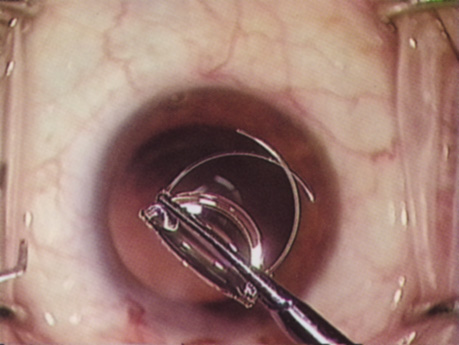

Despite numerous incision choices, one key factor is recommended for all cataract incisions: The incision should be self-sealing. A self-sealing incision decreases the risk of catastrophic expulsive hemorrhage if significant positive pressure develops for any reason. If positive pressure develops at any time during the procedure, simple removal of the instrument should prevent expulsion of the intraocular contents. Additionally, if properly placed and constructed, a self-sealing incision obviates the need for a suture, thereby avoiding suture distortion of the wound and induced astigmatism. Closure of the incision, regardless of incision type, should ensure that intraocular pressure or external pressure at the posterior lip of the incision, or elsewhere, will not cause wound leak. If leakage occurs, then stromal hydration or suture placement may be necessary. Whenever placing a suture across a cataract incision, the ocular tension should approximate normal pressure before tightening the suture. Doing so helps prevent the surgeon from overtightening the suture, which would induce astigmatism. ANTERIOR CAPSULOTOMY One of the most beneficial techniques developed over the last decade is capsulorrhexis. A continuous curvilinear anterior capsular opening helps prevent intraoperative and postoperative complications. With capsulorrhexis, mechanical strength of the capsular opening is superior to that in a can-opener capsulotomy; thus, a tear to the posterior capsule with subsequent vitreous loss is much less likely.96 Capsulorrhexis allows for nuclear manipulation with less risk of posterior capsule rupture. Cortex removal is made easier as well, because it becomes easier to differentiate cortical material from anterior capsule. Should a posterior capsular tear occur, sulcus fixation is more likely attainable with the presence of a clearly visible residual anterior capsular rim. Placement of both IOL haptics into the capsular bag is more certain with capsulorrhexis because the surgeon can more easily visualize the haptics gliding beneath the anterior capsular rim. Capsulorrhexis can be performed with a cystitome, capsulorrhexis forceps, or combination-type instruments. Regardless of which instrument is used, several principles can help the surgeon successfully complete capsulorrhexis. It is important to maintain the anterior chamber, because making the chamber shallow increases tension on the zonules and causes the tear to run peripherally. The authors recommend the use of a viscoelastic agent for maintaining chamber depth and, of course, for endothelial protection. Therefore, if the tear begins to run peripherally, the surgeon should redeepen the anterior chamber before attempting to redirect the tear. Additionally, folding the capsule margin can aid the surgeon in redirecting the tear more accurately (Fig. 10).